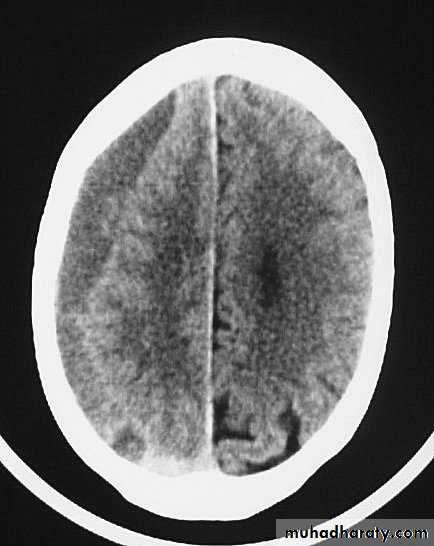

CT scans demonstrates contusions as small areas of haemorrhage in the cerebral parenchyma.

3. Cerebral Contusion

Resolution of Contusion